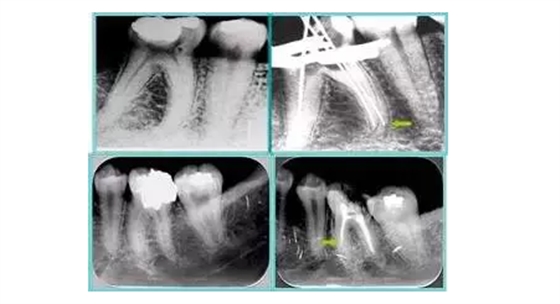

6. 術(shù)后 X 線片

術(shù)后 X 線片用來評定根管充填 長度、致密度(管壁清晰、側(cè)枝)等指標(biāo)。

左圖為根管充填術(shù)后 X 線片。圖中可見,根管充填較好。右下圖有白色小點(diǎn),為側(cè)方加壓導(dǎo)致糊劑擠出所致,表明根管充填比較致密。

致密、恰到好處的充填可去除干凈根管里感染灶,機(jī)體逐漸恢復(fù)。

多根牙時(shí)候需進(jìn)行偏移投照,正位投照無法說明具體哪根牙根管充填效果。 二、根管預(yù)備及充填要求